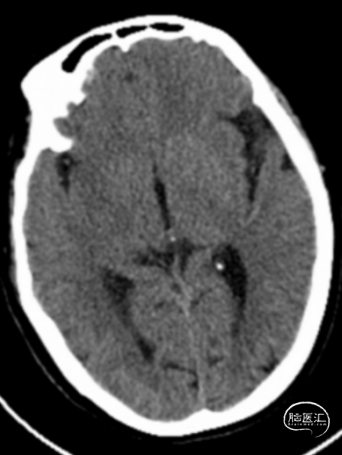

术前头颅CT示:颅内未见明显异常。

术后24小时头颅CT:右侧基底节区少量出血及低密度灶。